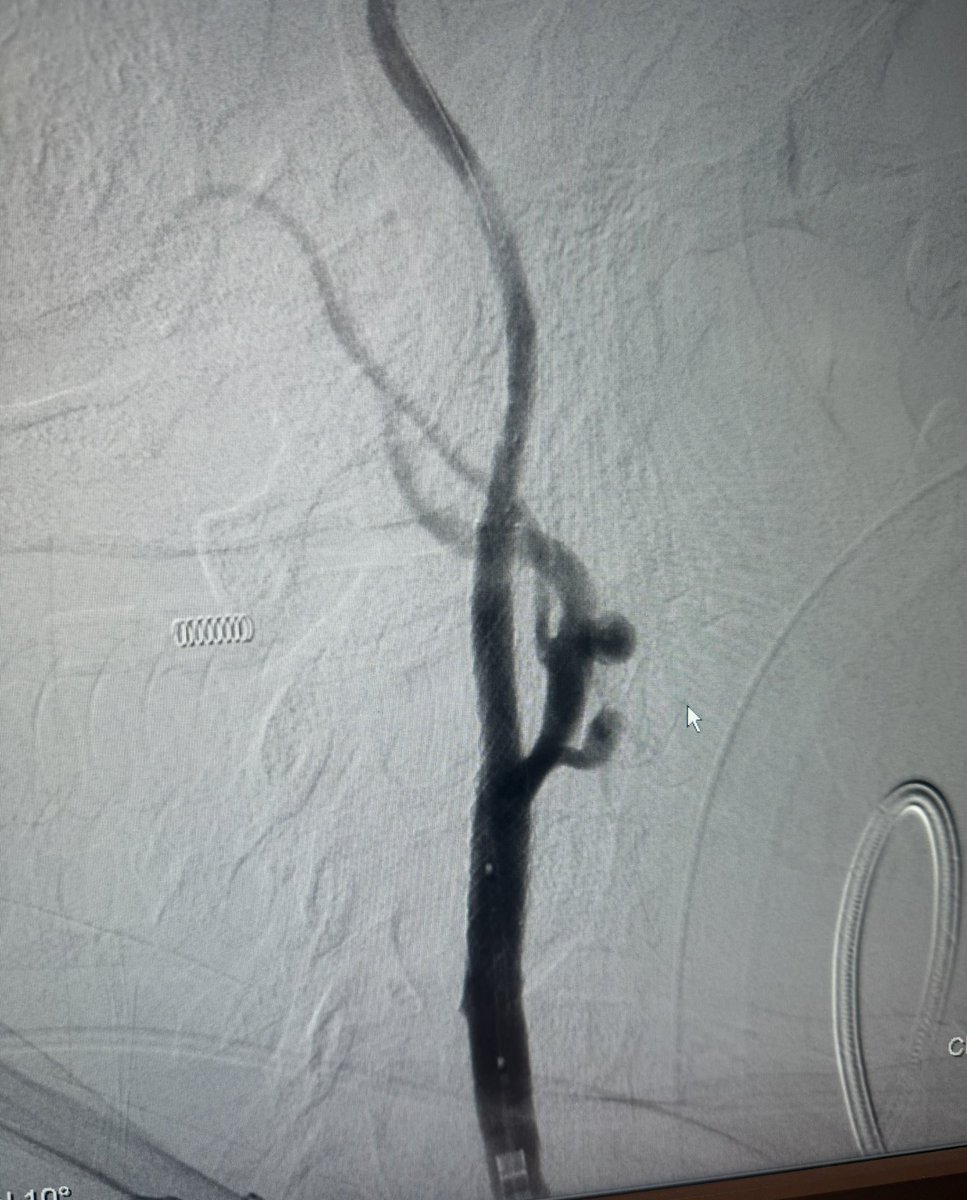

On maximum medical therapy for 2 years Although, Last week developed multiple posterior fossa infarction.(as patient was dependent on diseased RT) Chose LT which was near occlusion of V1/V2 total occlusion of V4, successful stenting using multiple Coronary DES

On maximum medical therapy for 2 years

Although,

Last week developed multiple posterior fossa infarction.(as patient was dependent on diseased RT)

Chose LT which was near occlusion of V1/V2 total occlusion of V4, successful stenting using multiple Coronary DES